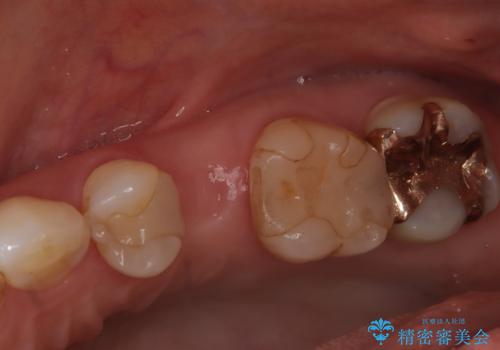

今回の症例では、骨の量が十分あったため、比較的短期間で治療を完了することができました。インプラントを使用することで、安定した咬み合わせが実現し、患者様は痛みもなく安心して食事を楽しむことができるようになりました。

インプラント治療は、しっかりとした診断と計画のもとに行われることで、自然な見た目と快適な噛み心地を取り戻すことができます。もし、歯を失ってお困りの方や、他の治療法で満足していない方がいらっしゃいましたら、ぜひ一度ご相談ください。